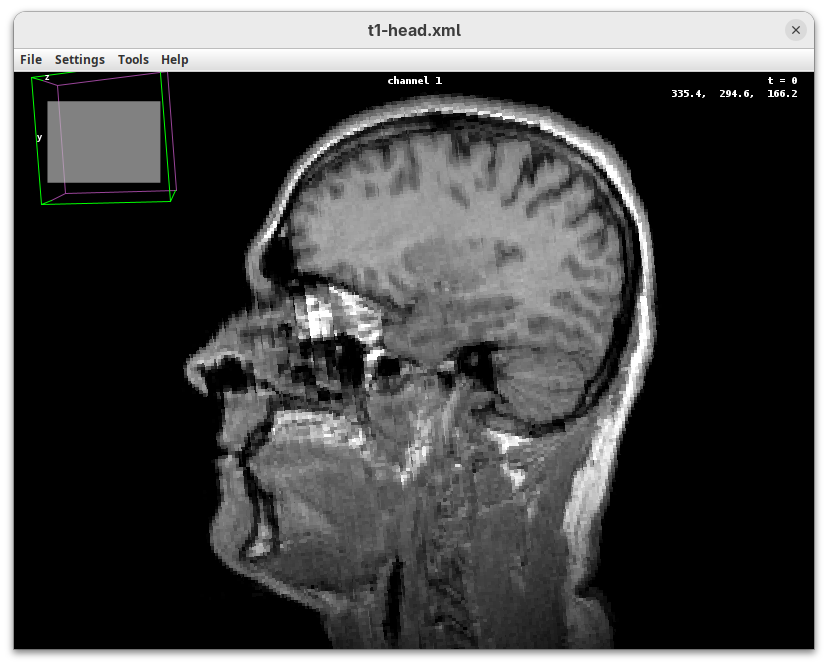

BigDataViewer

BigDataViewer (Pietzsch et al. 2015) is one of the most important tools for visualizing large, multidimensional datasets. It provides a simple and intuitive interface and shortcuts to swiftly navigate through your sample even on a regular laptop. This is possible because of the underlying file format used by BigDataViewer: the XML/HDF5 combo. Therefore, before opening the plugin, we must convert our dataset.

Plugins>BigDataViewer>Open XML/HDF5and select thet1-head.xml.

The BigDataViewer interface will open showing an optical section of the head sample.

Getting familiar with BigDataViewer is an essential skill for navigating large 3D datasets. It’ll also be important for the multiview registration pipeline. So, take the time to learn the basic commands and shortcuts. It is nicely intuitive. The BigDataViewer’s page on the ImageJ Docs has the official documentation and we can also go to Help > Show Help for an up-to-date overview.

Some of the movements to try:

Left-click and drag: turn the sample around the mouse pointer at any arbitrary angle.Right-click and drag: move the sample in the XY plane (of the view).Scroll: move through the Z plane (of the view). UseShift+Scrollto move fast.Ctrl+Shift+Scroll: zoom in or out.

But, most importantly, are the commands to put your sample back to its original orientation or along any of the original dimension axes:

Shift+Z: orient the sample on the XY plane.Shift+X: orient the sample on the ZY plane.Shift+Y: orient the sample on the ZX plane.

Finally, a visual tip. The default interpolation between image slices is nearest-neighbors. Press I to activate the tri-linear interpolation to obtain a much smoother (and improved) data visualization.